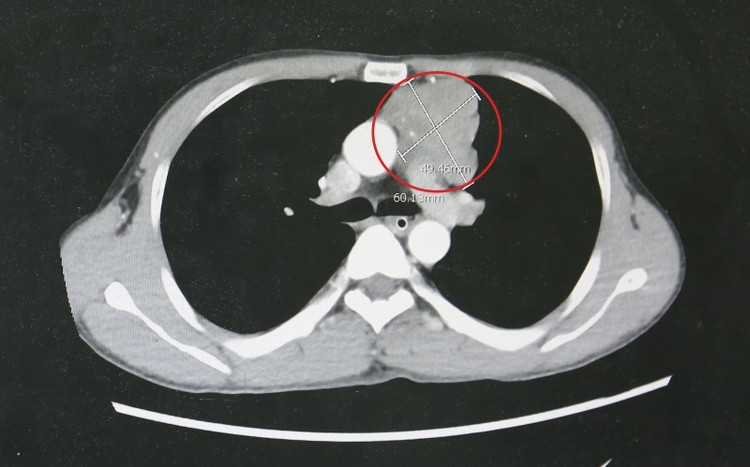

Qua thăm khám lâm sàng, cơ lực chi chỉ còn 3/5, phản xạ kém, cơ lực cổ yếu, cơ hô hấp suy giảm. Kết quả chụp cắt lớp vi tính lồng ngực phát hiện khối u trung thất trước kích thước lớn khoảng 4x6cm, xâm lấn thần kinh hoành, bên trong có vôi hóa.

Khối u tuyến ức kích thước lớn của bệnh nhân gây nhược cơ - Ảnh BVCC

Qua ba đường rạch nhỏ trên thành ngực, bác sĩ đưa dụng cụ nội soi vào khoang màng phổi trái, quan sát thấy tuyến ức phì đại, khối u có đường kính khoảng 6 cm, tăng sinh mạch, bám chặt vào thùy trên phổi trái và ôm sát quai động mạch chủ.